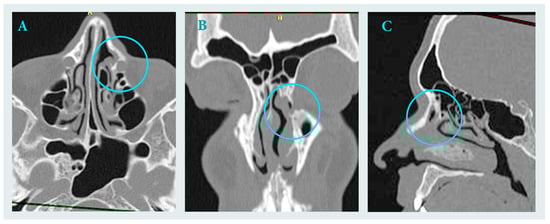

Endoscopic Management of an Inflammatory Lesion Suspected of Being a Brown Tumor of the Frontal Process of the Maxilla—Case Report

Surgeries 2025, 6(4), 107; https://doi.org/10.3390/surgeries6040107 - 2 Dec 2025

The study reports a diagnostic challenge involving an inflammatory lesion mimicking a brown tumor. A 23-year-old male patient was referred for treatment of a cystic lesion in the left frontal process of the maxilla and ethmoid region. The leading symptoms were hemoptysis and

The study reports a diagnostic challenge involving an inflammatory lesion mimicking a brown tumor. A 23-year-old male patient was referred for treatment of a cystic lesion in the left frontal process of the maxilla and ethmoid region. The leading symptoms were hemoptysis and chronic sinus inflammation. Endoscopic surgery was performed under general anesthesia, including curettage and drainage of the lesion into the middle nasal meatus. Histopathological examination revealed chronic inflammatory and fibrotic changes with hemosiderin deposits and CD68(+) histiocytes, findings that could suggest a brown tumor. However, subsequent laboratory investigations excluded this diagnosis. Postoperative healing was uneventful, with complete resolution of symptoms. This report highlights the importance of distinguishing inflammatory from metabolic bone lesions in the paranasal sinuses and underscores the critical role of histopathological evaluation in differentiating true neoplasms from inflammatory pseudotumors.